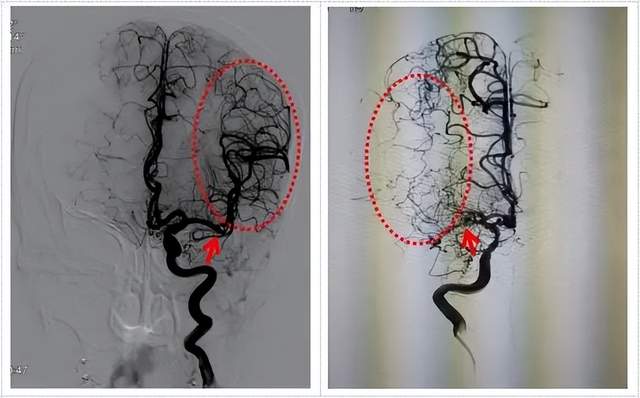

考虑到病情的凶险性,入院后,李凯还主任医师和李征副主任医师急诊为赵叔完善了脑血管造影检查,证实了赵叔颅内不仅长了多个动脉瘤,出乎意料的是还合并了烟雾病。这种情况对于已经68岁的赵叔来说可是雪上加霜。

术前DSA检查颅内多发动脉瘤

正常血管 烟雾病

面对该患者前交通动脉和右侧大脑前动脉多发动脉瘤合并烟雾病,无论是开颅动脉瘤夹闭还是血管内介入栓塞治疗难度都比较大。